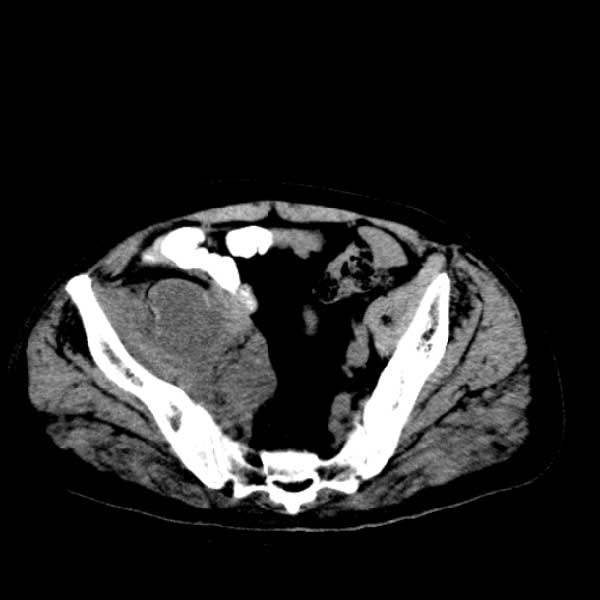

标题: CT13513:男 71 腹部疼痛20余天,近几天高热就诊,骨窗未见异 [打印本页]

标题: CT13513:男 71 腹部疼痛20余天,近几天高热就诊,骨窗未见异

考虑右侧腰大肌脓肿,向右髂窝、右腹股沟流注。

支持化脓性阑尾炎伴右髂窝脓肿、腰大肌腰方肌脓肿形成。

考虑腹腔及盆腔化脓性炎症,累及右侧髋关节及腹股沟区.

首先考虑化脓性阑尾炎伴腰大肌、腰方肌脓肿,不除外回盲部结核。

回盲部癌待排除。

患者肠镜检查考虑结肠癌,病理证实

患者肠镜检查考虑结肠癌,病理证实。肺部ct可见多发结节,考虑转移